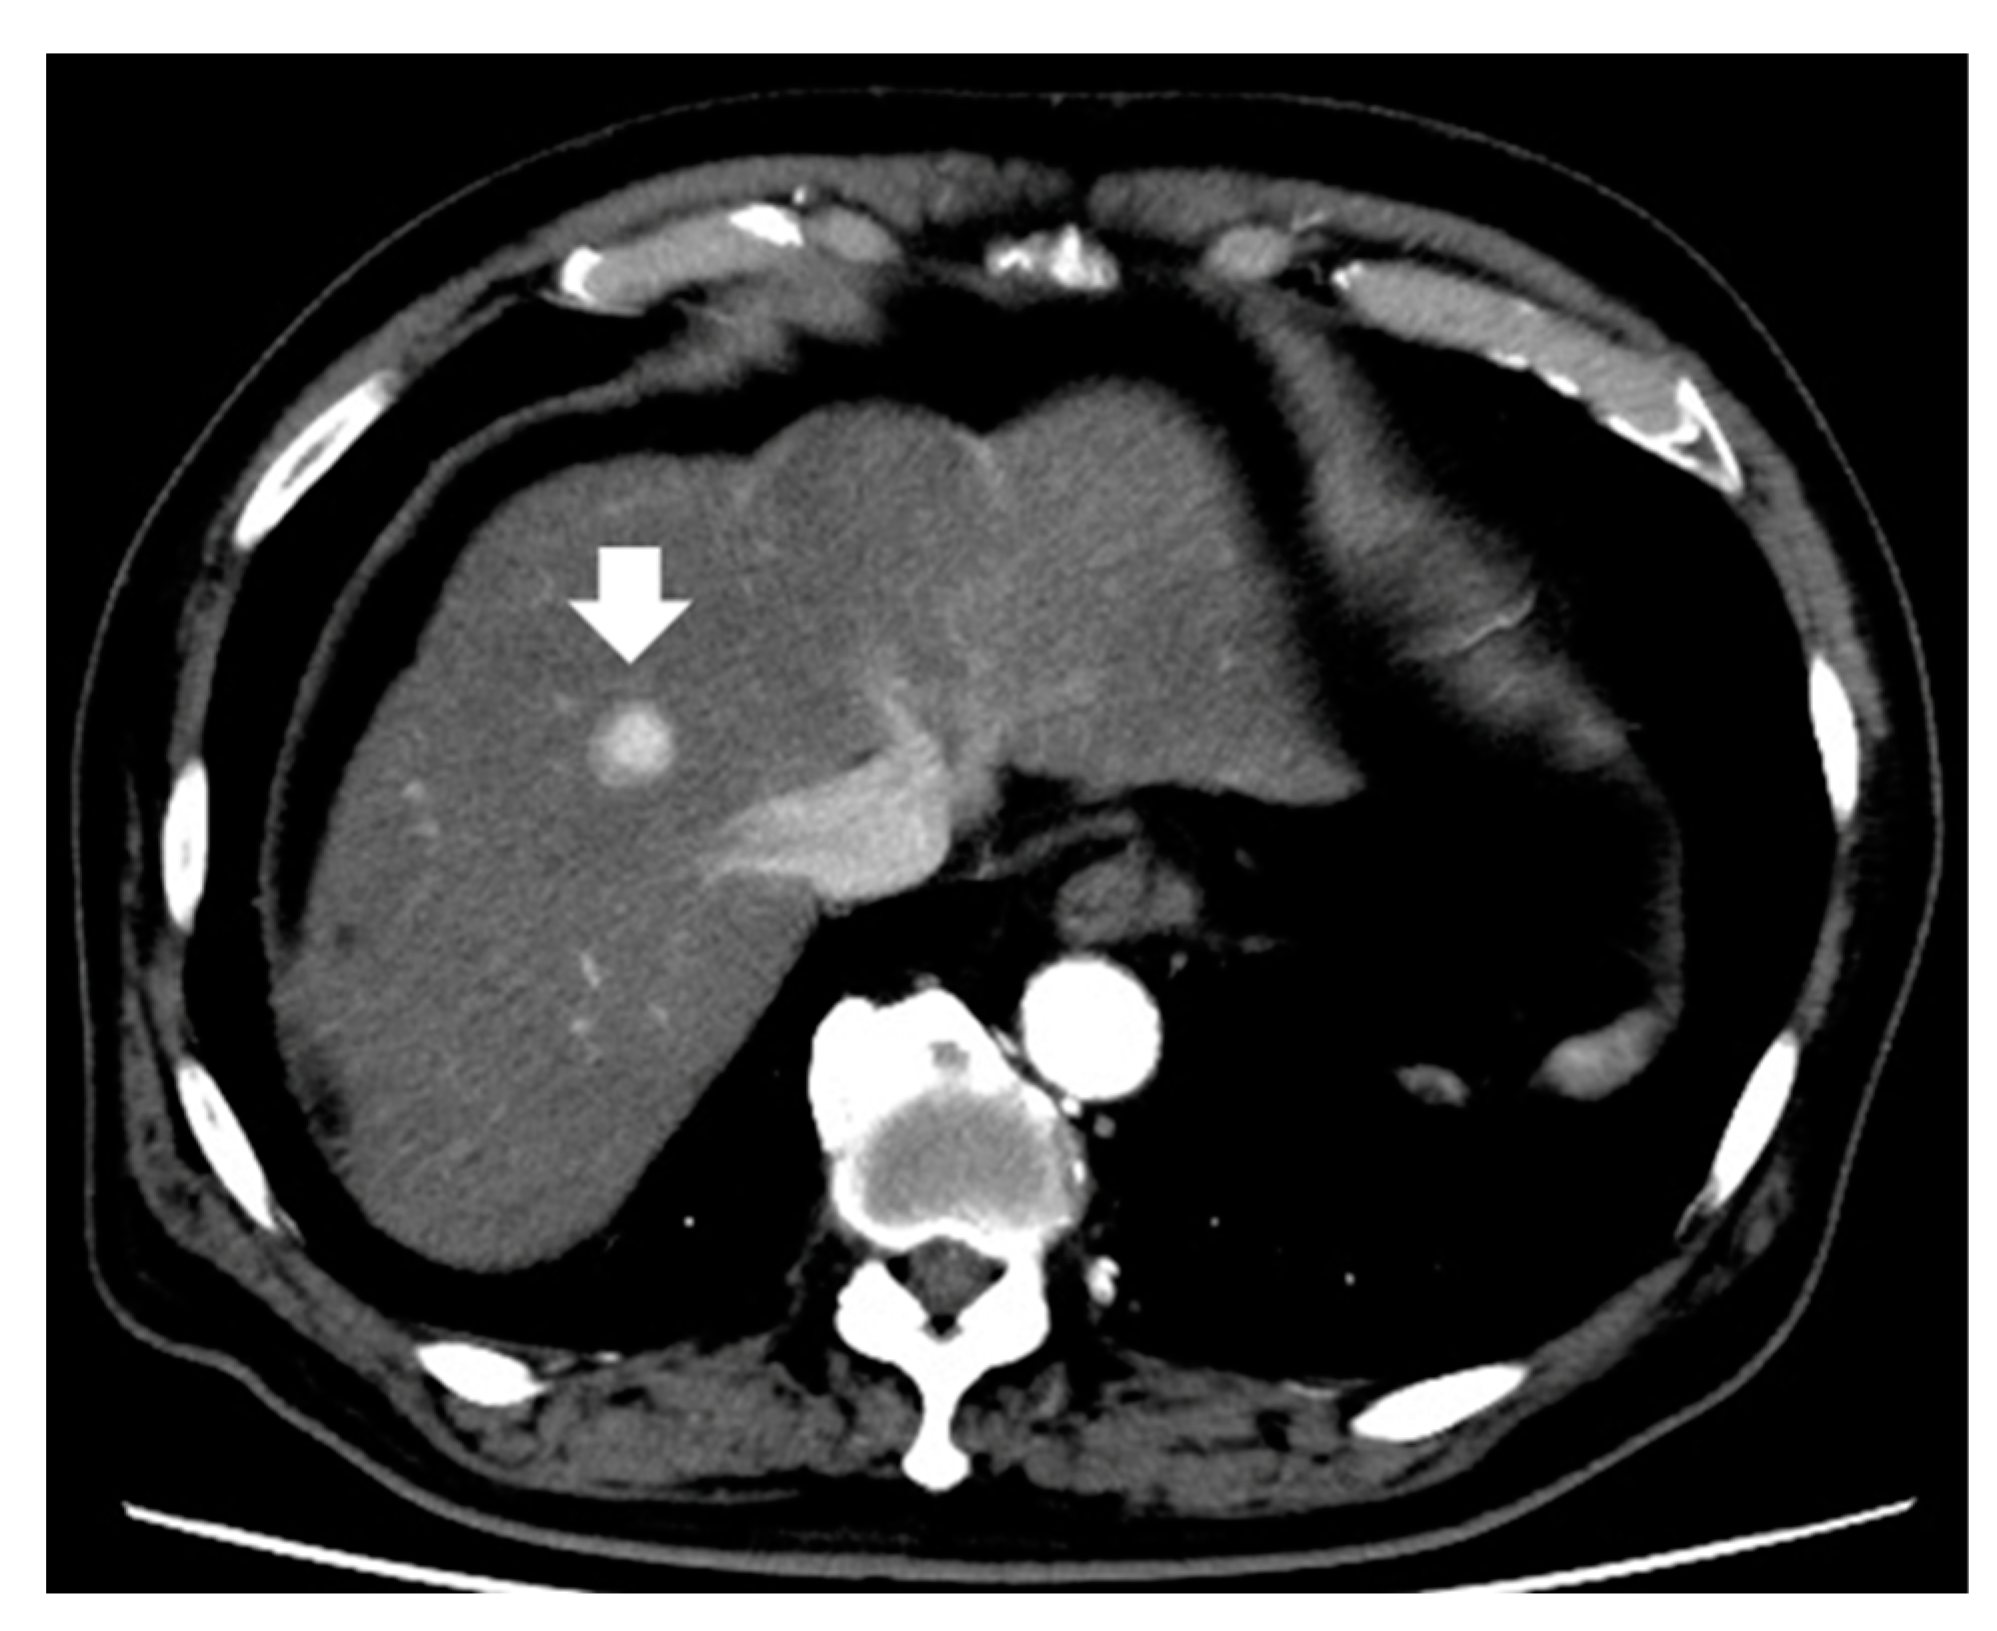

3.1. Enhancement Pattern in the Arterial Phase

- Kawamura, Y.; Ikeda, K.; Hirakawa, M.; Yatsuji, H.; Sezaki, H.; Hosaka, T.; Akuta, N.; Kobayashi, M.; Saitoh, S.; Suzuki, F.; et al. New classification of dynamic computed tomography images predictive of malignant characteristics of hepatocellular carcinoma. Hepatol. Res. Off. J. Jpn. Soc. Hepatol. 2010, 40, 1006–1014. [Google Scholar] [CrossRef]

- Kawamura, Y.; Ikeda, K.; Seko, Y.; Hosaka, T.; Kobayashi, M.; Saitoh, S.; Kumada, H. Heterogeneous type 4 enhancement of hepatocellular carcinoma on dynamic CT is associated with tumor recurrence after radiofrequency ablation. AJR Am. J. Roentgenol. 2011, 197, W665–W673. [Google Scholar] [CrossRef]

- Nakachi, K.; Tamai, H.; Mori, Y.; Shingaki, N.; Moribata, K.; Deguchi, H.; Ueda, K.; Inoue, I.; Maekita, T.; Iguchi, M.; et al. Prediction of poorly differentiated hepatocellular carcinoma using contrast computed tomography. Cancer Imaging Off. Publ. Int. Cancer Imaging Soc. 2014, 14, 7. [Google Scholar] [CrossRef] [PubMed]

- Shimizu, R.; Tamai, H.; Mori, Y.; Shingaki, N.; Maeshima, S.; Nuta, J.; Maeda, Y.; Moribata, K.; Muraki, Y.; Deguchi, H.; et al. The arterial tumor enhancement pattern on contrast-enhanced computed tomography is associated with primary cancer death after radiofrequency ablation for small hepatocellular carcinoma. Hepatol. Int. 2016, 10, 328–339. [Google Scholar] [CrossRef] [PubMed]

| Kawamura et al. [40] | 191 | Solitary and ≤3 cm | Resection (60) RFA (131) | Outcome (recurrence) | The type 4 enhancement pattern was an independent factor for recurrence (HR, 27.68; 95% CI, 6.82–112.33; p < 0.001). |

| Nakachi et al. [41] | 223 | Early stage | Biopsy Resection | Differentiation | HCC with enhancement with non-enhanced area predicted poorly differentiation. Predictive value as follows; sensitivity was 85%, specificity was 76%, positive predictive value was 93%, negative predictive value was 97%, and accuracy was 77%. |

| Shimizu et al. [42] | 226 | ≤3 tumors and ≤3 cm | RFA | Outcome (recurrence, OS) | Heterogeneous enhancement pattern was one of the independent factors for critical recurrence (HR, 2.753; 95% CI, 1.453–5.219; p = 0.002) and related cancer death (HR, 2.369; 95% CI, 1.187–4.726; p = 0.014). |